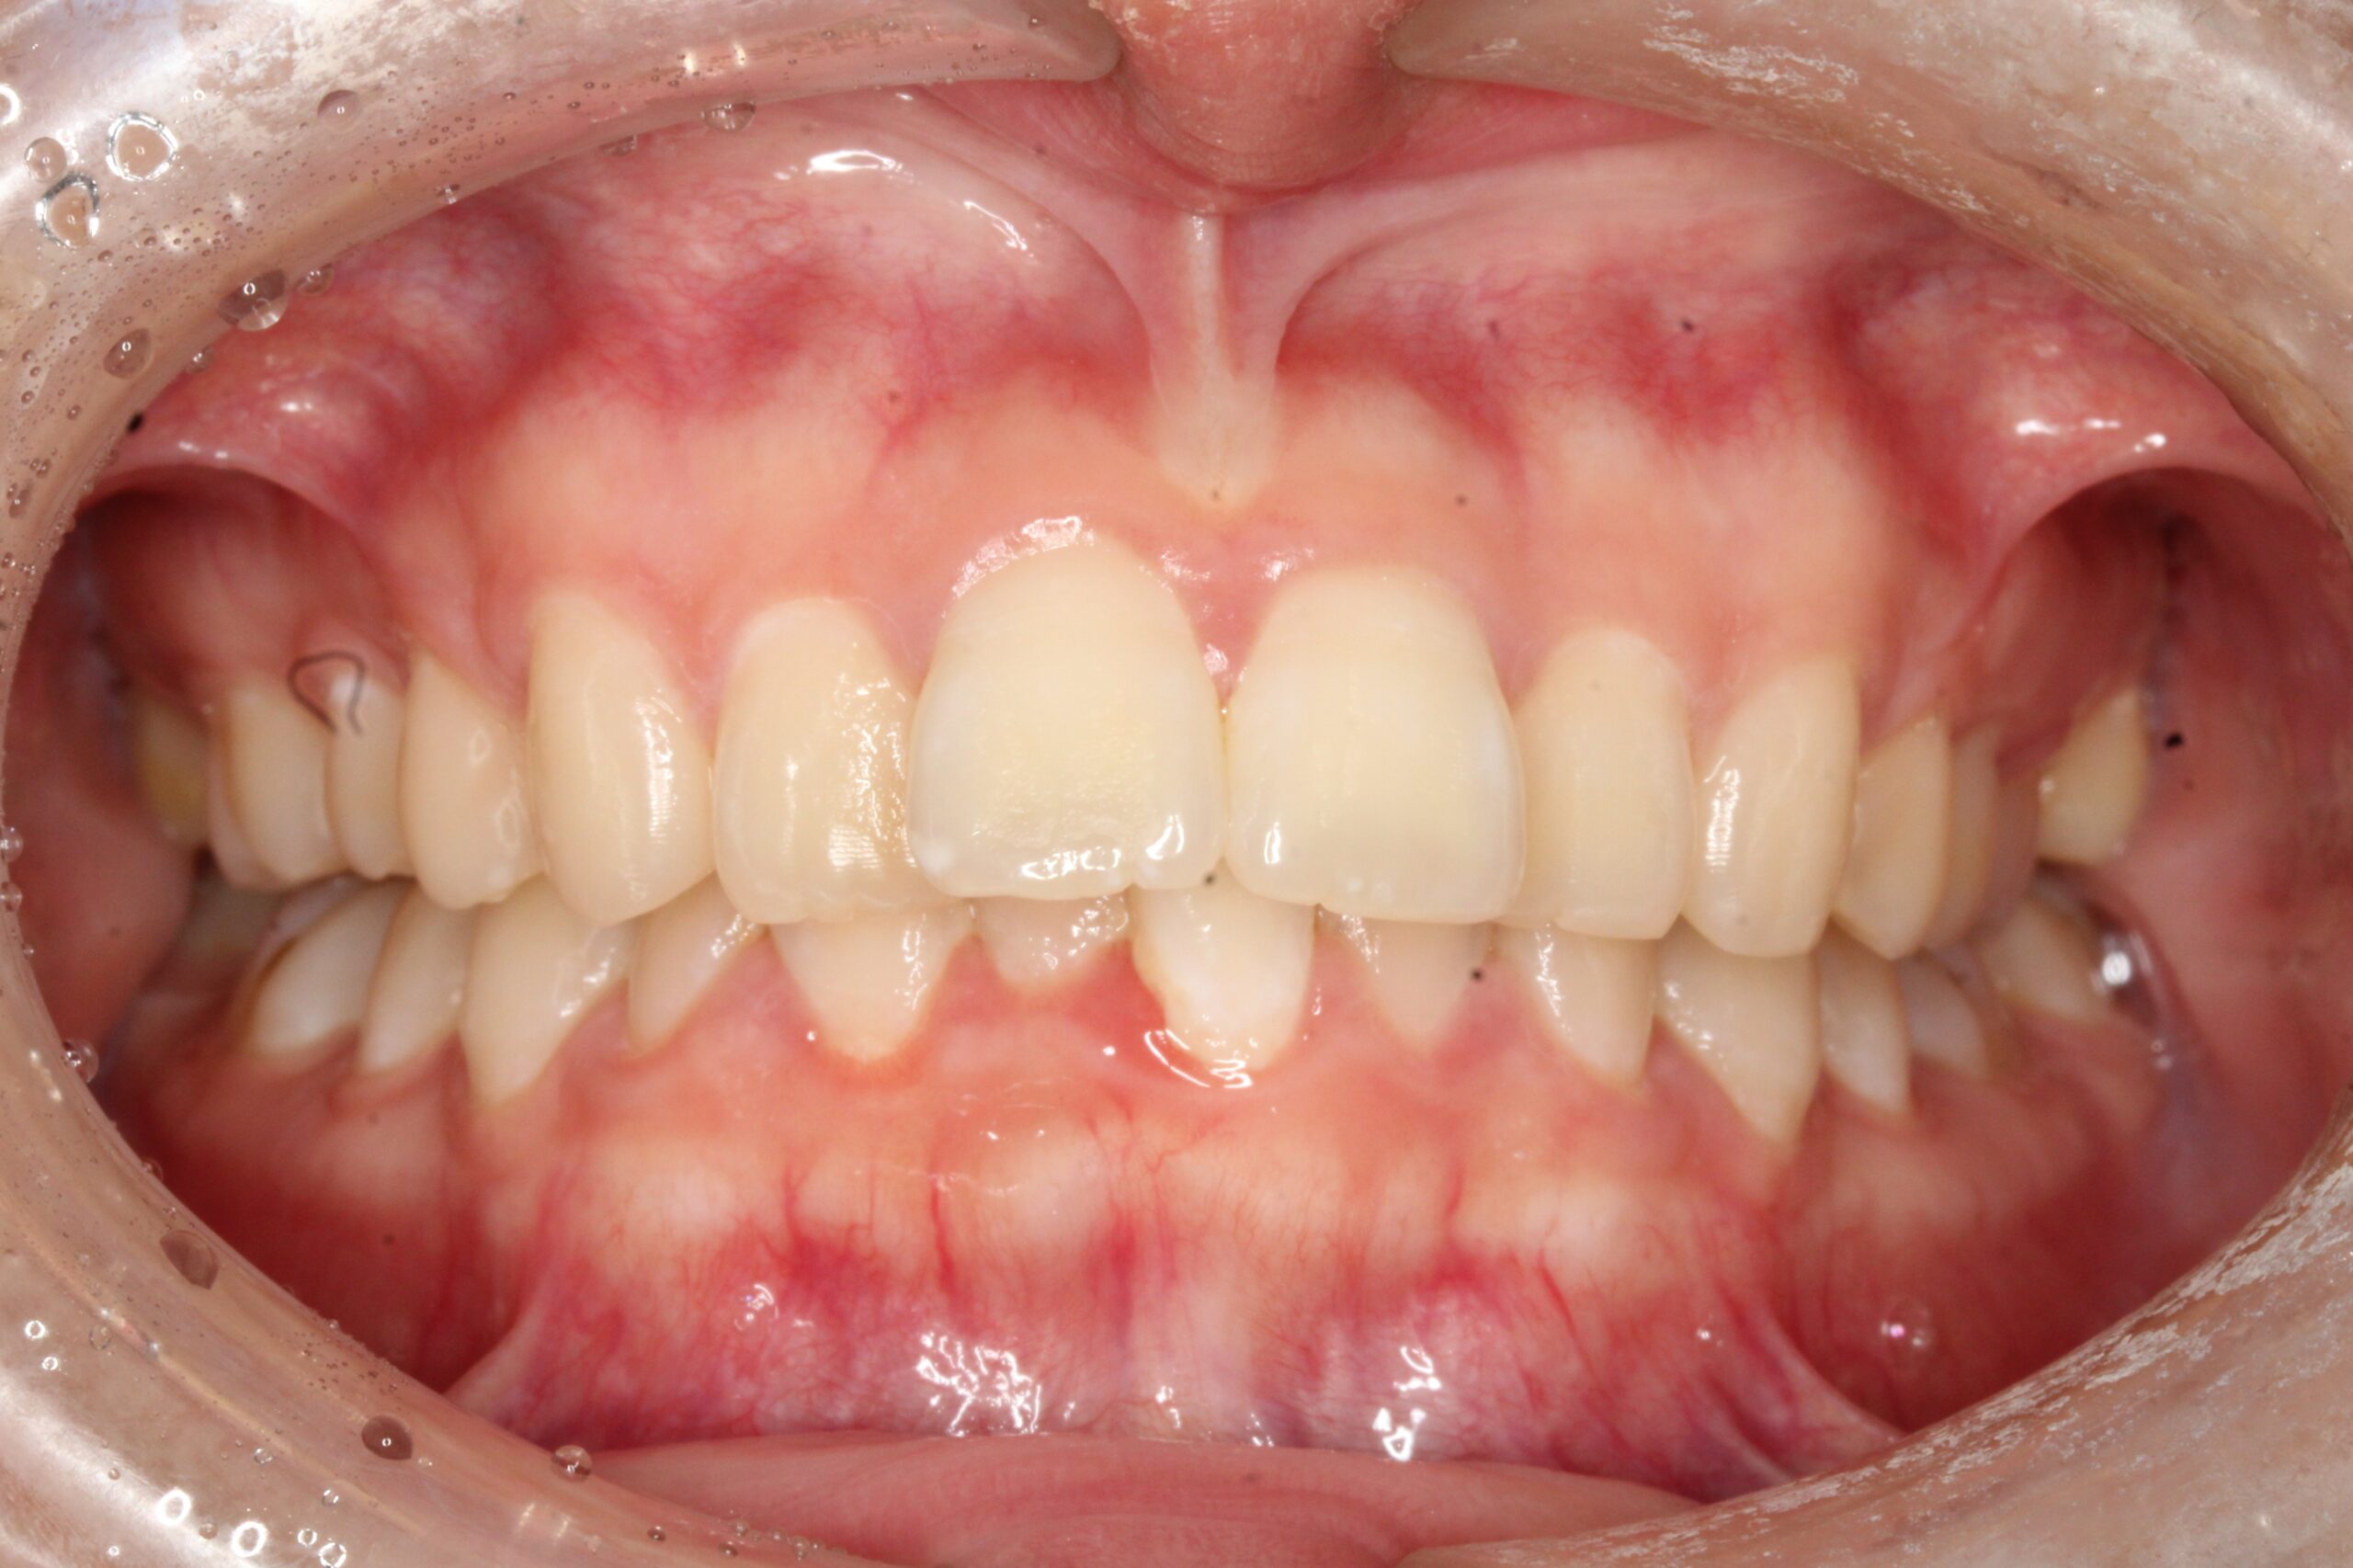

矯正術前:正面